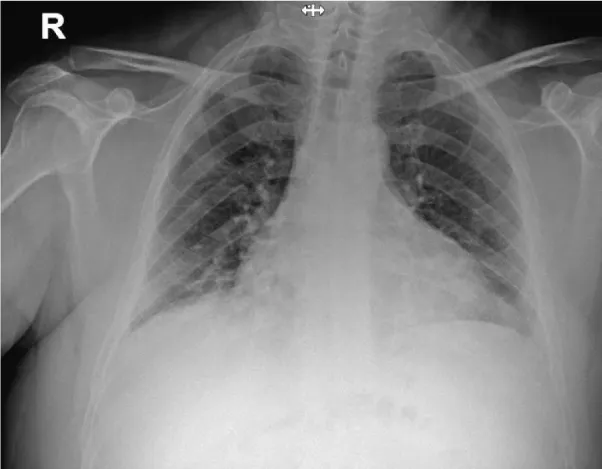

On admission the patient complains of dyspnea and diarrhea. On physical examination he was alert with fever (39.3ºC), increased respiratory rate 30 breaths/minute and decreased O2 saturation- 92% measured in room air). Heart rate was 69 beats/minute and blood pressure was 133/75 mmHg. Laboratory blood tests revealed: White Blood Cell (WBC) count - 19.21 K/micl, thrombocytes-122 K/micl, and increased serum C-Reactive Protein (CRP)-7.3 mg/dL, ferritin-504.8 ng/mL and D-dimer levels -333 ng/mL. PaO2/FiO2 ratio was 118, FiO2 of100. Chest x-ray on admission revealed bilateral patchy consolidation (Figure 1). The patient was categorized as a moderate to severe disease since he had pneumonia, respiratory distress and O2 saturation<94%.